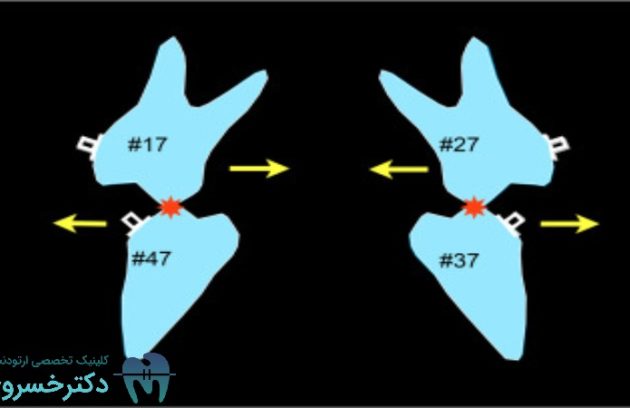

پروتکل Sendai SF در روش Surgery First